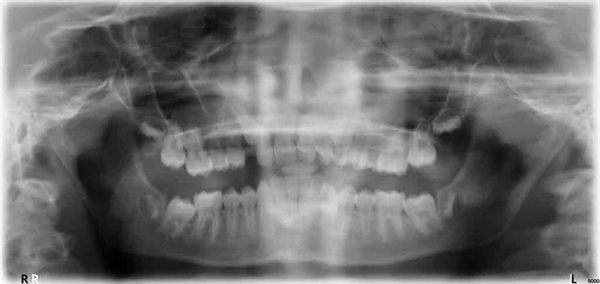

A 15-year-old female presented as a transfer patient after four years of active treatment elsewhere. Pre-treatment records taken when she was nearly 12 showed a case that appeared manageable—near-Class I occlusion, adequate maxillary arch space, and an ectopically positioned upper right canine that did not seem unusually difficult to address (Figs. 1–3). What arrived at the new practice was something considerably more complex.

Fig. 1